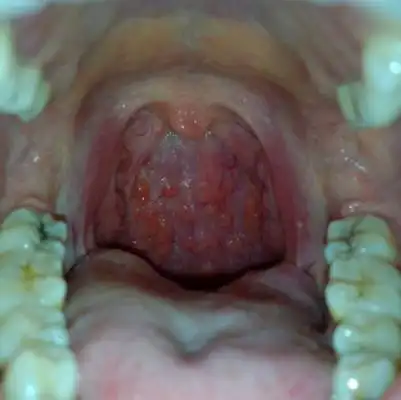

喉咙长了个囊肿图片 (21)